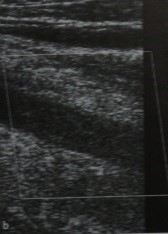

Острый тромбоз бедренной вены с тотальной окклюзией ее просвета. Цветовое допплеровкое сканирование в поперечной(а) и продольной (b) плоскостях. При визуализации определяется незначительно дилатированный, гипоэхогенный просвет вены , допплеровский сигнал отсутствует.